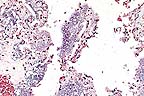

Septic and necrotizing placentitis due to Salmonella arizona in a sheep. (HE, 400X, 54K).

Abundant intratrophoblastic and extracellular gram-negative bacilli in the placenta of a sheep. (Brown-Hopps', 1000X, 39K)

Contributor's Diagnosis and Comments: Lesions were restricted to lung (moderate alveolitis) and placenta (severe necrotizing placentitis with large numbers of Salmonella organisms in trophoblasts and placental blood vessels); due to Salmonella arizonae.

The presence of massive numbers of organisms in trophoblasts in an ovine placenta is highly suggestive of Coxiella infection. However, Coxiella is typically restricted to the trophoblasts and does not invade deeper placental tissues. Further query of the owner revealed that the sheep were housed in a barn that formerly housed turkeys, a possible source of the Salmonella. Salmonella arizonae can be recovered from the small and/or large intestine of sheep in the absence of intestinal lesions (1), and these sheep may have been carriers of the organism.

Grossly, the chorioallantois is thickened by amber, fibrin-containing fluid. Portions of the caruncle may remain adherent to the cotyledon. Histologically, there is mineralization of the trophoblast cells, interstitium of the villi, and chorioallantoic arcade. The villi are often expanded by large numbers of Salmonella, and, in some villi, neutrophils. Dilated capillaries, immediately under the sloughed trophoblast cells in the arcade zone, are expanded by bacteria and resemble large rounded trophoblast cells filled with bacteria. The fetus is often free of lesions; however, bacteria may occasionally be found colonizing the airway epithelium. Suppurative hepatitis has also been reported in fetuses from Salmonella-induced abortions.